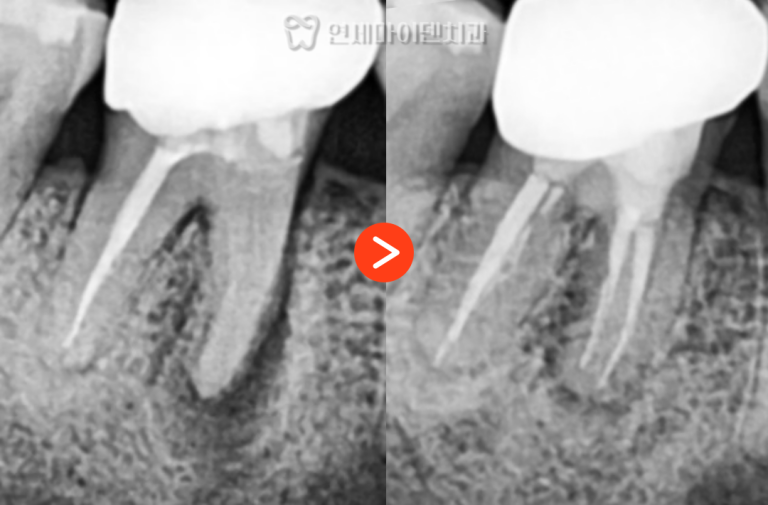

신경치료를 통해 염증 부위를 제거하고,

레진으로 내부를 밀봉한 뒤 크라운을 수복했습니다.

치근까지 염증이 진행되기 전 내원하신 덕분에

발치 없이 치아를 보존할 수 있었습니다.